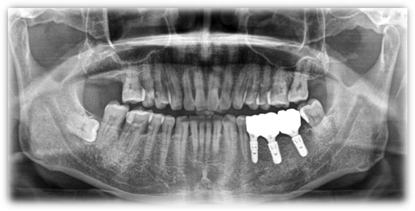

植牙案例分享:

C先生左下缺兩顆牙齒加上第二大臼齒因蛀牙剩下殘根,讓他長期習慣用右邊進食,這樣也使臉部肌肉不對稱,俗稱 [ 大小臉 ] ,嚴重可能臉部歪斜,外觀受到影響。

透過醫師幫病患做骨質再生手術以及植牙重建,讓患者能夠恢復原本的咀嚼功能。

人工植牙

治療前

治療後

▲ 本影像僅供醫療說明參考,療效因個人狀況不同,應由專業醫師評估